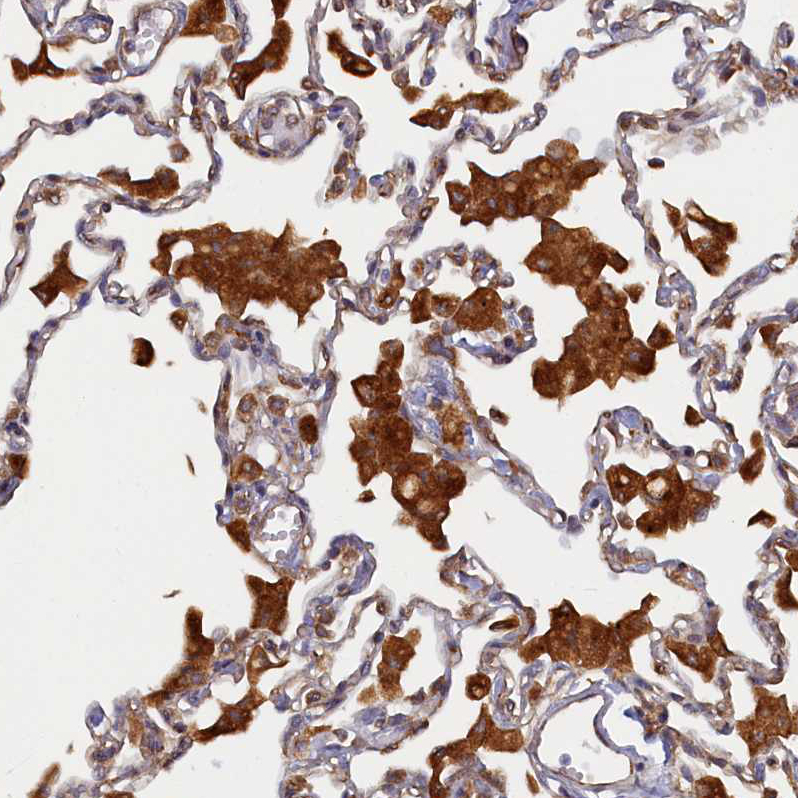

Immunohistochemical staining of human lung shows strong cytoplasmic positivity in macrophages.